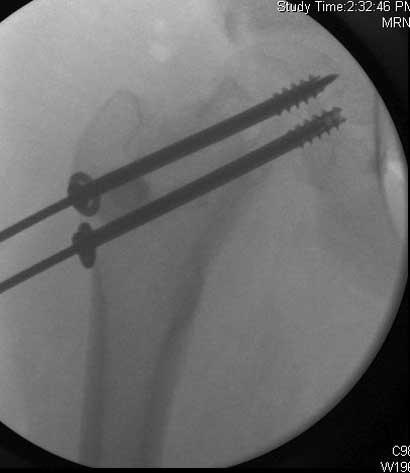

Severe slip treated with arthroscopic Dunn type of femoral neck osteotomy

Severe slip treated with arthroscopic Dunn type of femoral neck osteotomy, reduction and fixation.